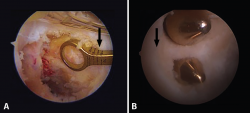

El patrón de lesión del LCP se divide en 3 tipos según su imagen en RM: lesión parcial o intrasustancia (Figura 6A), lesión completa (Figura 6B) y fractura avulsión a nivel de la inserción tibial (Figura 6C)(13,14). La mayoría de las lesiones completas se producen en la porción media del ligamento, que no se llega a visualizar correctamente en los planos axial y coronal, por lo que el gold standard es la evaluación de las imágenes en cortes sagitales(13,14).

reaca.28373.fs2101003-figura6.png

Figura 6. A: corte sagital de resonancia magnética (RM) en secuencia T2 donde se observa una rotura parcial; B: rotura total del ligamento cruzado posterior (LCP); C: corte sagital de RM en T1 de la rodilla izquierda. La flecha blanca indica la avulsión del LCP con fragmento óseo en la inserción tibial.